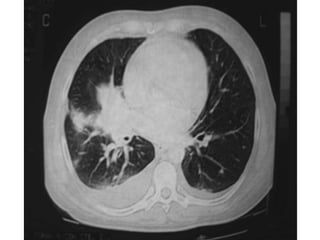

Macroscopia

-Los ¾ son de formacion cercana al hilio (central)

-Los perifericos son mas adenocarcinomas.

-Pueden crecer:

1. En luz bronquial

2. Infiltrar bronquio y tejido circundante

3. Formar masa intraparenquimatosa.

-Son tumores duros, que pueden dar hemorragia y necrosis

(por tanto pueden hacer cavitaciones).

-Se pueden extender a pleura, pericardio, cavidad toracica.

Robbins 7ma

Macroscopia -Los ¾ sonde formacion cercana al hilio (central) -Los perifericos son mas adenocarcinomas. -Pueden crecer: 1. En luz bronquial 2. Infiltrar bronquio y tejido circundante 3. Formar masa intraparenquimatosa. -Son tumores duros, que pueden dar hemorragia y necrosis (por tanto pueden hacer cavitaciones). -Se pueden extender a pleura, pericardio, cavidad toracica. Robbins 7ma